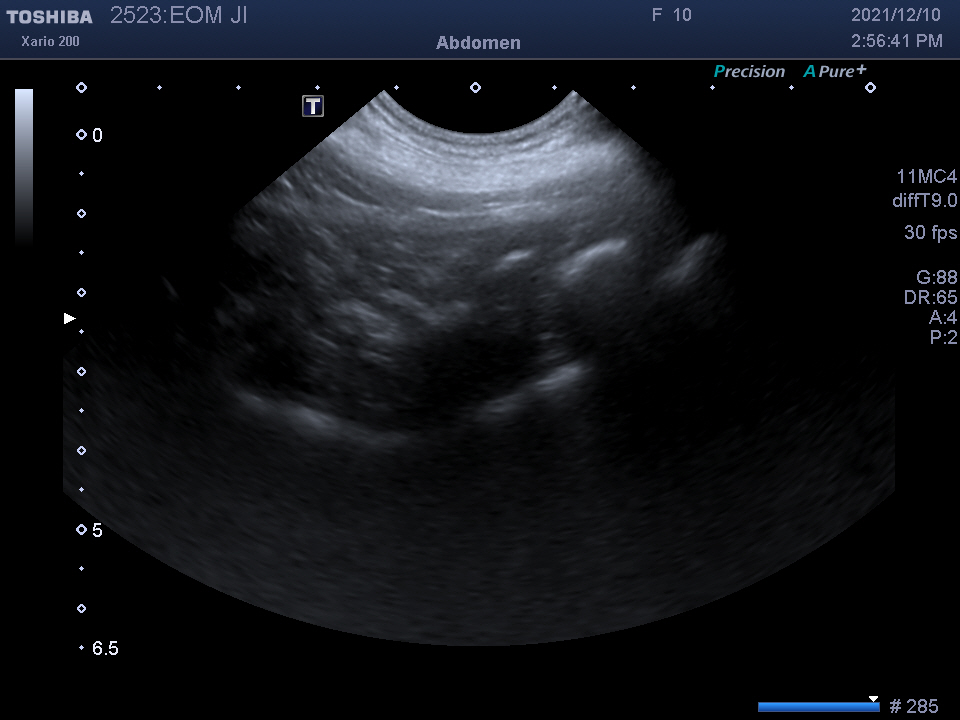

복강 내 장기를 자세히 알 수 있는

복부 초음파 검사를 진행하였습니다.

검사 결과를 종합하여 자궁 축농증이라는 진단을 받았습니다.